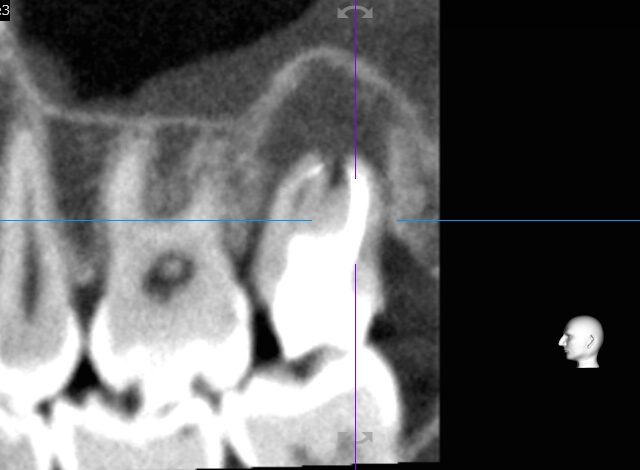

根管治療